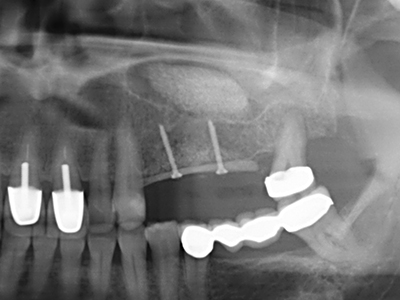

Fig. 11: El ortopantomograma posoperatorio presenta el aumento vertical y la elevación del suelo del seno.

Fig. 12: Después de seis meses de cicatrización se muestra una cresta maxilar vital con unas dimensiones suficientes en todas las direcciones.

Fig. 17: Tomografía computarizada de un osteoma de crecimiento progresivo ...

Fig. 17b: justo al lado del canal alveolar con irritación nerviosa (vista lateral y coronal).